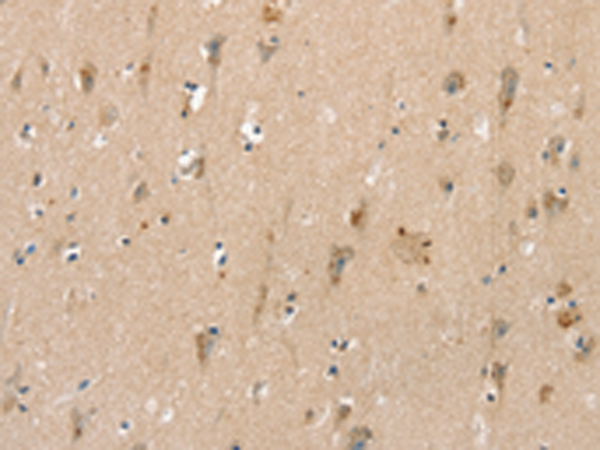

分类: 科研抗体货号: P12173别名:应用: IHC反应种属: Human, Mouse